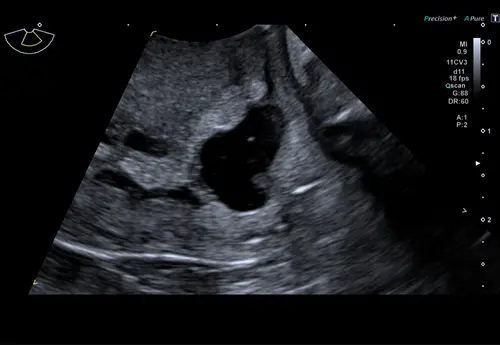

Ik heb veel onderzoek gehad door verschillende redenen en ik heb vaak verdikt slijmvlies, verdikte eileider etc. Ook heb ik verschillende cystes in zowel mijn baarmoeder als daarbuiten. Endomestriose bleek bij mij de oorzaak. En doordat het eitje niet altijd kan springen of niet goed kan springen wisselt bij mij m'n cyclus met regelmaat. Nooit een zwangerschapstest hiervoor gedaan dus dat weet ik niet.